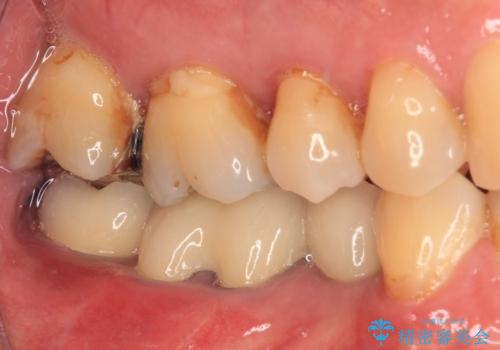

- 奥歯の欠損部へのインプラント治療を希望して来院された患者様です。

抜歯をしてから長年経過しており、レントゲンからは十分に骨があることが分かっていたため、速やかに治療を開始することとしました。

インプラント治療に当たり、手前の銀歯2本の審美回復も希望されたため、3歯のオールセラミッククラウンによる補綴治療を行うこととしました。

通常、奥歯を抜歯した状態で長年放置すると、咬み合う歯が伸びてきて、咬み合わせが乱れてしまうことが多いです。そのような場合には、部分的な矯正治療などが必要となるのですが、こちらの患者様は幸運なことに咬み合わせが乱れていなかったため、インプラント埋入から速やかに補綴治療を行うことができました。